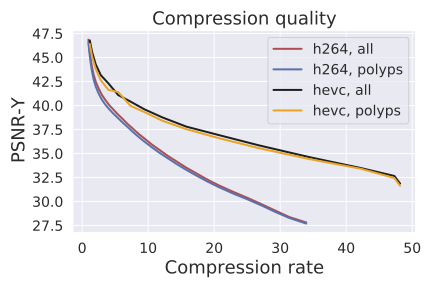

Compression metrics: We evaluate frame quality using two standard image metrics: PSNR-CbCr and PSNR-Y. PSNR is the standard "Peak Signal to Noise Ratio" derived from the mean squared error between pixels in the original frame and the compressed frame. The value of the pixels depends on the type of PSNR computation:“CbCr" corresponds to PSNR between chroma of the frames, and “Y" corresponds to PSNR between luminance of the frames.

Compression quality: Figure 1 (middle) shows the compression rate versus frame quality distribution for H264 and HEVC. Importantly, we see that H264 and HEVC compress the most medically relvant frames statistically significantly worse: treating each QP value separately, a two-sided Kolmogorov-Smirnov test between distribution of PSNR-CbCr shows that the frame quality is lower for polyp frames than for all frames. For each QP value, , , H264 (HEVC) maximum p-value over all tests is (), mean test statistic (). For the same test with PSNR-Y, see the Appendix. Figure 2 top two rows show the lowest quality compressed frames inside the body according to PSNR-CbCr, with and without polyps (for the absolute worst quality compressed frames, see the Appendix).

Detector performance: Figure 1 (right) shows the polyp detector performance as a function of compression rate. Videos can be compressed by factors of 4.7x and 7.3x before dropping below 99% the base performance for H264 and HEVC respectively, 10.6x and 20.8x for 95%, and 14.3x and 30.4x for 90%. In addition to getting better frame quality and higher compression rates, the detector performs 0.057 AUC better and a 29% relative improvement111relative improvement defined as on HEVC videos compared to H264, as the same compression rate. The same holds in the “practical" regime of compression rates that achieve at least 95% the AUC of the original model: AUC is on average 0.26 AUC improved with a 23% relative improvement in AUC.